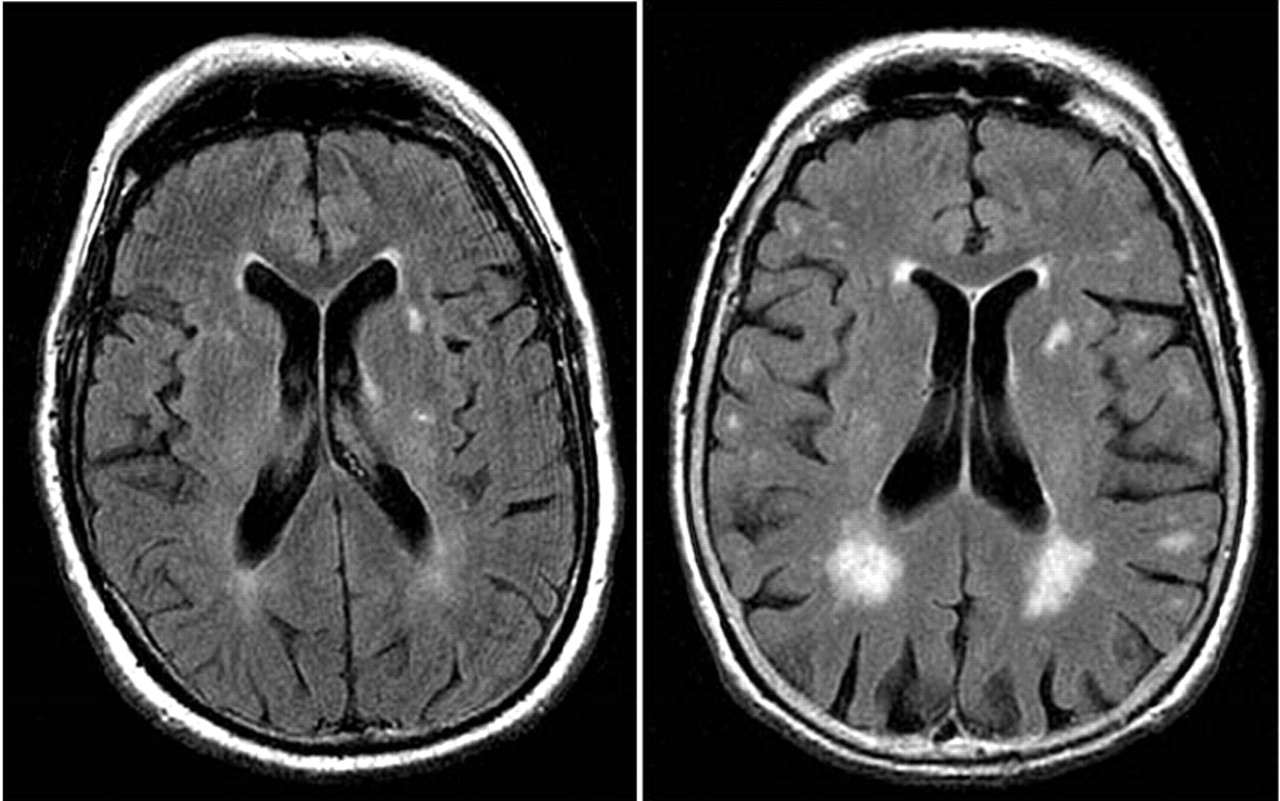

Brain MRI - Multiple Sclerosis - YouTube

Brain MRI - Multiple Sclerosis Woodson Jones. Subscribe Subscribed Unsubscribe 38 38. Loading Multiple Sclerosis-MRI Lesion-Breea's Story - Duration: 3:08. breeareneebeatsms 16,012 views. VERY POWERFUL BRAIN HEALING SOUNDS : MUST TRY - Duration: ... View Video

Magnetic Resonance Imaging (MRI) Findings In White Matter ...

ECommons@AKU Department of Radiology Medical College, Pakistan February 2008 Magnetic resonance imaging (MRI) findings in white matter disease of brain ... Read Here

MRI Brain - Guilford Radiology

MRI BRAIN MRI has long been the modality of choice for almost all non- traumatic brain imaging. This includes imaging of congenital abnormalities, cancer, white matter disease, vascular malformations, and infectious disease. ... View Document